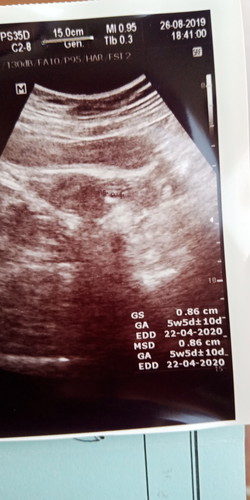

USG BEDA DOKTER HASILNYA BEDA BIKIN BINGUNG

tanggal 26 saya usg di doktr A sudah dikatakan hamil 5minggu 5hari selang 10hr skrg tanggal 6 saya usg di dokter B tidak nampak apa apa bagaimana ini bund? adakah yang pernah dngr pengalaman seperti saya ini??

Usia segitu biasanya memang cuma ada kantongnya mba, janinnya belum keliatan. Coba 2-3 minggu lagi usg lagi